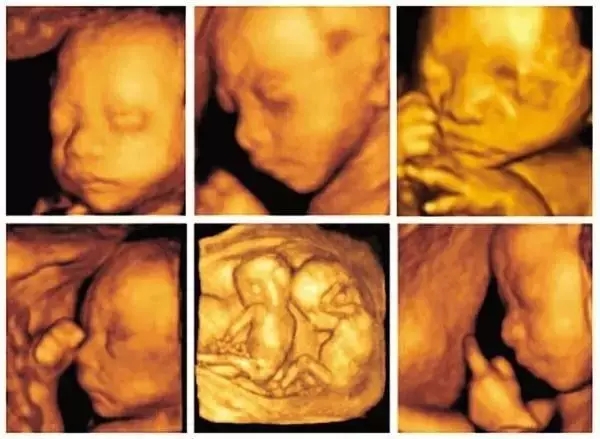

会诊中心成立以来,不断引进和升级设备。在原有的基础上又新增了多台超声诊断仪、彩色超声诊断仪,新引进的GE四维彩超,无论从超声技术、设备分辨率或成像效果来说都有着以往超声不可比拟的优势,让超声检查更具专业性。

超声技术作为胎儿畸形筛查的主要方法,具有无创性、可重复性等优点,可观察各个孕期胎儿形态及结构改变,可早期发现胎儿畸形,对优生优育,提高人口素质具有重要价值。广东冯鎏祥会长介绍说,“广东省围产保健基地超声专家会诊中心”的成立,进一步提升了佛山地区产前超声诊断水平,对降低出生缺陷,促进优生优育有重要意义。

据不完全统计,会诊中心成立一年来,产前四维彩超筛查及会诊数量高达10000例!